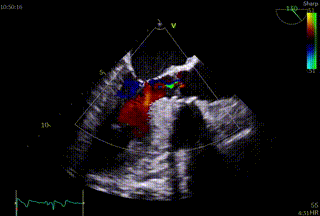

右足位,瓣膜形态,冠脉灌注良好

左头位造影

术前与术后超声,瓣口面积从0.6cm²提升至 2.2cm²,血流动力学优异。